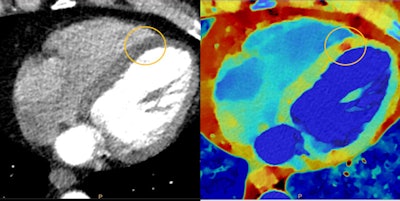

Indeed, Spectral CT 7500 is designed to be used in spectral mode for all clinical applications, including cardiology, oncology, neurology, and trauma. Philips believes that broader use of dual-energy imaging can produce cost savings by reducing follow-up tests that are needed to resolve inconclusive scans.

For example, a single-shot coronary CT angiography scan in spectral mode could rule out the need to send a patient on to a nuclear stress test or echocardiography, according to Boussebaa.